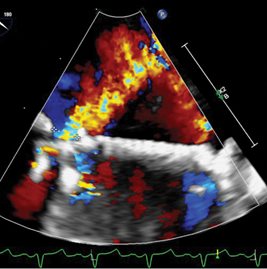

Subsequent TEE reveals a moderate-to-severe paravalvular leak along the posterior aspect of the mechanical mitral valve (see Fig. 4).

Fig. 4. Transesophageal echocardiogram demonstrating mitral PVL. Short axis view (top) of the prosthetic mitral valve from the left atrium using three-dimensional (3D) echo. Color doppler at the 6 o’clock position represents regurgitant flow outside of the mitral prosthesis during systole. Long axis view (bottom) of the prosthetic mitral valve demonstrating the same PVL.